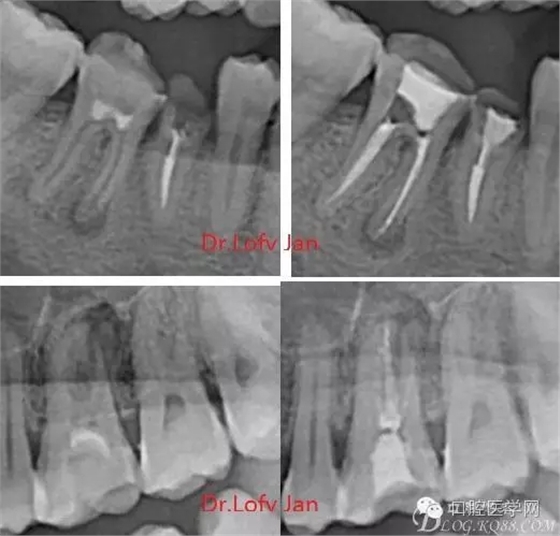

曲面斷層片在未試尖根管治療中的病例整理

前言:自己做的一些曲面斷層片在未試尖根管治療中的病例整理,發(fā)現(xiàn)問題很多包括自身的,技術(shù)的,還有設(shè)備的問題,予以總結(jié)整理并期待進(jìn)一步提高。

根管治療術(shù)是牙體牙髓疾病治療中最復(fù)雜和最關(guān)鍵的治療項(xiàng)目。根管充填材料抵達(dá)根尖、并能嚴(yán)密堵塞根尖孔,是確保根管治療效果的關(guān)鍵指標(biāo)。為了保證根管充填到位,醫(yī)生需要在術(shù)前照牙片以了解牙根根管的數(shù)量、彎曲程度和長(zhǎng)度,在術(shù)中有時(shí)需要插針照牙片來精確測(cè)量根管長(zhǎng)度,術(shù)后必須照牙片以確定是否根管充填到位,如果欠填或超填,就需要重新充填、重新照牙片確認(rèn),直到根管充填到位。所以,在患者接受根管治療時(shí)有時(shí)會(huì)反復(fù)照牙片。

《數(shù)字化根尖片、曲面斷層片、CBCT測(cè)量牙齒長(zhǎng)度準(zhǔn)確性的比較研究》文中顯示:平行投照數(shù)字化根尖片影像長(zhǎng)度和牙齒實(shí)際長(zhǎng)度之間無顯著性差異(P0.05);數(shù)字化曲面斷層片影像長(zhǎng)度和牙齒實(shí)際長(zhǎng)度之間有顯著性差異(P0.05),平均失真率為17.05%。CBCT冠狀面測(cè)量結(jié)果中除上頜前磨牙區(qū)、下頜前磨牙區(qū)與真實(shí)長(zhǎng)度差異無統(tǒng)計(jì)學(xué)意義(P0.05)外,其余6個(gè)分區(qū)差異均有統(tǒng)計(jì)學(xué)意義(P0.05);矢狀面測(cè)量結(jié)果中上頜磨牙區(qū)、下頜磨牙區(qū)、下頜前磨牙區(qū)、下頜尖牙區(qū)、下頜前牙區(qū)與真實(shí)長(zhǎng)度比較差異均有統(tǒng)計(jì)學(xué)意義(P0.05)。結(jié)論平行投照數(shù)字化根尖片較曲面斷層片和CBCT能更加精確地反映牙齒的真實(shí)長(zhǎng)度。

病例分析:曲面斷層片在x線輔助診斷與檢查中目前大多數(shù)文獻(xiàn)和著作都建議只能作為初診拍片檢查手段,不能作為終末疾病的確診與手術(shù)療效的評(píng)價(jià)指標(biāo),臨床大部分中小型門診都因?yàn)樵O(shè)備不齊全導(dǎo)致信息偏差很大。